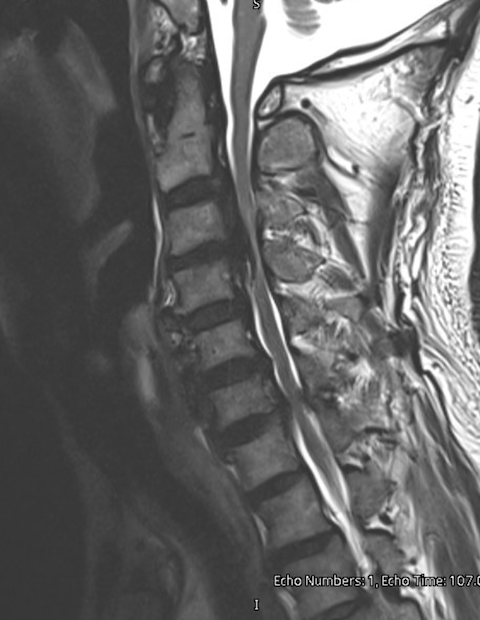

• MRI of the cervical spine

MRI shows spinal cord compression and can reveal signal changes within the cord.

MRI scan of a human lumbar spine showing vertebrae, intervertebral discs, and spinal cord.

• MRI shows the spinal cord directly.

• It suggests stress or injury to the spinal cord.